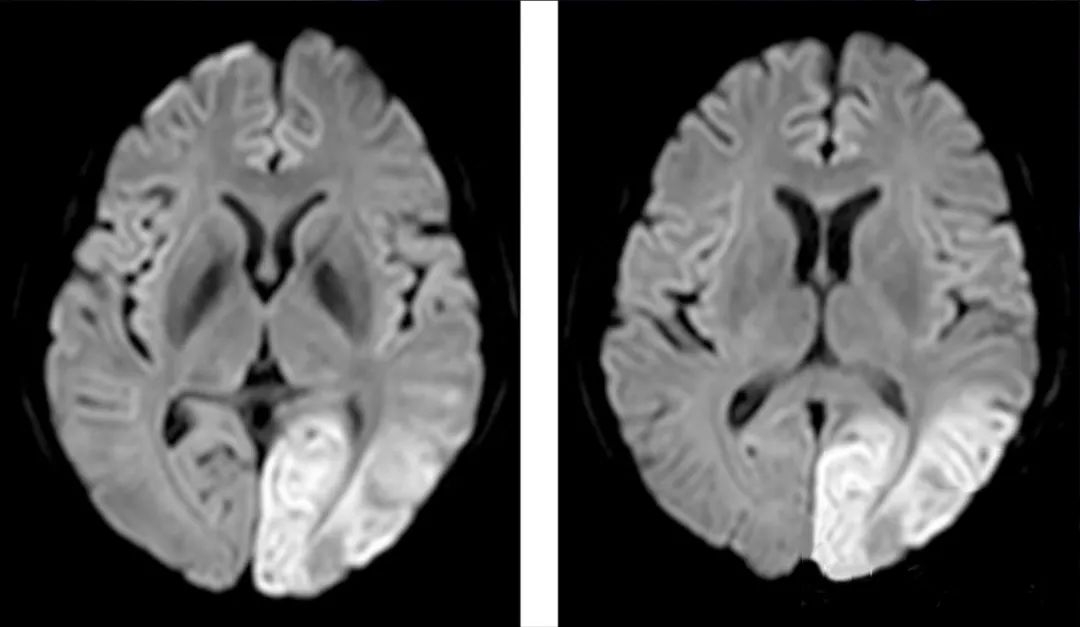

经过一系列的抢救,大梦从昏迷中苏醒过来,初步诊断为“脑炎”。但是单纯的脑炎,无法解释她体内居高不下的乳酸值。经过磁共振检查发现,她的大脑里有一片白雾一样的游走性病灶,这片白雾还在不断扩散、向外蔓延。就像大梦血液几乎停止流动的真相一样,摸不着也抓不到。

右下角白色的地方

就是大梦磁共振上的游走性病灶

根据调取的病史,医生发现大梦曾在两年前出现过肢体乏力的症状,再结合她大脑磁共振上的游走性病灶,排除掉糖尿病、恶性肿瘤等可能导致乳酸升高的原因,只剩下最后一种可能。医生们给她做了个肌肉活检,最终确诊为:线粒体脑肌病(MELAS型)。